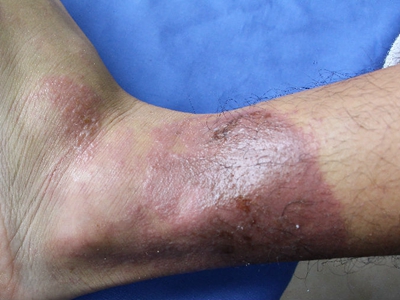

职业性光变应性接触性皮炎一般是指职业性变应性接触性皮炎或职业性光接触性皮炎,是在劳动中接触光敏物,如沥青、煤焦油、氯丙嗪等,并受日光照射引起的皮肤炎性反应,属于职业性皮炎的一种类型,皮损多发生在暴露部位。

职业性光变应性接触性皮炎的皮损常发生于接触光敏物的暴露部位,且受光照后5-14天或更久后出现,致敏物再接触后一般在24小时内发病。

皮疹表现为急性湿疹样,即水肿性红斑,上有小丘疹或水疱,皮损边缘常不清楚,可出现在非照射部位皮肤以及全身,自觉瘙痒,可伴灼痛,一般无全身症状。